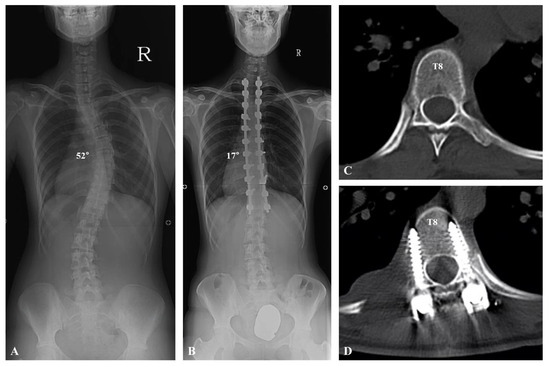

| Postoperative (°) | 17.4 ± 5.4 | 21.0 ± 5.9 | 0.043 |

| Correction rate (%) | 70.2 ± 5.9 | 65.3 ± 8.9 | 0.04 |

| 3-month follow-up (°) | 17.5 ± 5.1 | 21.5 ± 4.8 | 0.046 |